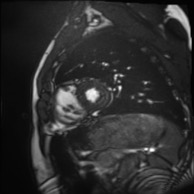

Medical data often exhibits long-tail distributions with heavy class imbalance, which naturally leads to difficulty in classifying the minority classes (i.e., boundary regions or rare objects). Recent work has significantly improved semi-supervised medical image segmentation in long-tailed scenarios by equipping them with unsupervised contrastive criteria. However, it remains unclear how well they will perform in the labeled portion of data where class distribution is also highly imbalanced. In this work, we present ACTION++, an improved contrastive learning framework with adaptive anatomical contrast for semi-supervised medical segmentation. Specifically, we propose an adaptive supervised contrastive loss, where we first compute the optimal locations of class centers uniformly distributed on the embedding space (i.e., off-line), and then perform online contrastive matching training by encouraging different class features to adaptively match these distinct and uniformly distributed class centers. Moreover, we argue that blindly adopting a constant temperature $\tau$ in the contrastive loss on long-tailed medical data is not optimal, and propose to use a dynamic $\tau$ via a simple cosine schedule to yield better separation between majority and minority classes. Empirically, we evaluate ACTION++ on ACDC and LA benchmarks and show that it achieves state-of-the-art across two semi-supervised settings. Theoretically, we analyze the performance of adaptive anatomical contrast and confirm its superiority in label efficiency.

翻译:医学数据经常呈现长尾分布和重度类别不平衡,这自然导致在对少数类别(即边界区域或罕见目标)进行分类时出现困难。最近的研究在长尾情况下通过装备医学影像的无监督对比标准,明显改进了半监督医学图像分割。然而,在标记的数据部分中,类别分布也极为不平衡,因此它们的表现如何仍不清楚。在本研究中,我们介绍一种采用自适应解剖对比度改进的对半监督医学分割行动的框架(ACTION++)。具体来说,我们提出了一种自适应监督对比损失,它首先在嵌入空间上计算出不同类别的优化位置(即离线),然后通过鼓励不同类别之间的特征与这些不同和均匀分布的类别中心相适应的在线对比匹配训练来进行自适应匹配。此外,我们认为,在长尾医疗数据中盲目采用常温度$\tau$不是最优的,因此通过一个简单的余弦计划来使用动态$\tau$来产生更好的多数类别和少数类别之间的分离。在实证方面,我们在ACDC和LA基准测试中评估ACTION++,并展示了其在两种半监督设置下的最新成果。从理论上讲,我们分析了自适应解剖对比度的性能,并证实了它在标签效率上的优越性。